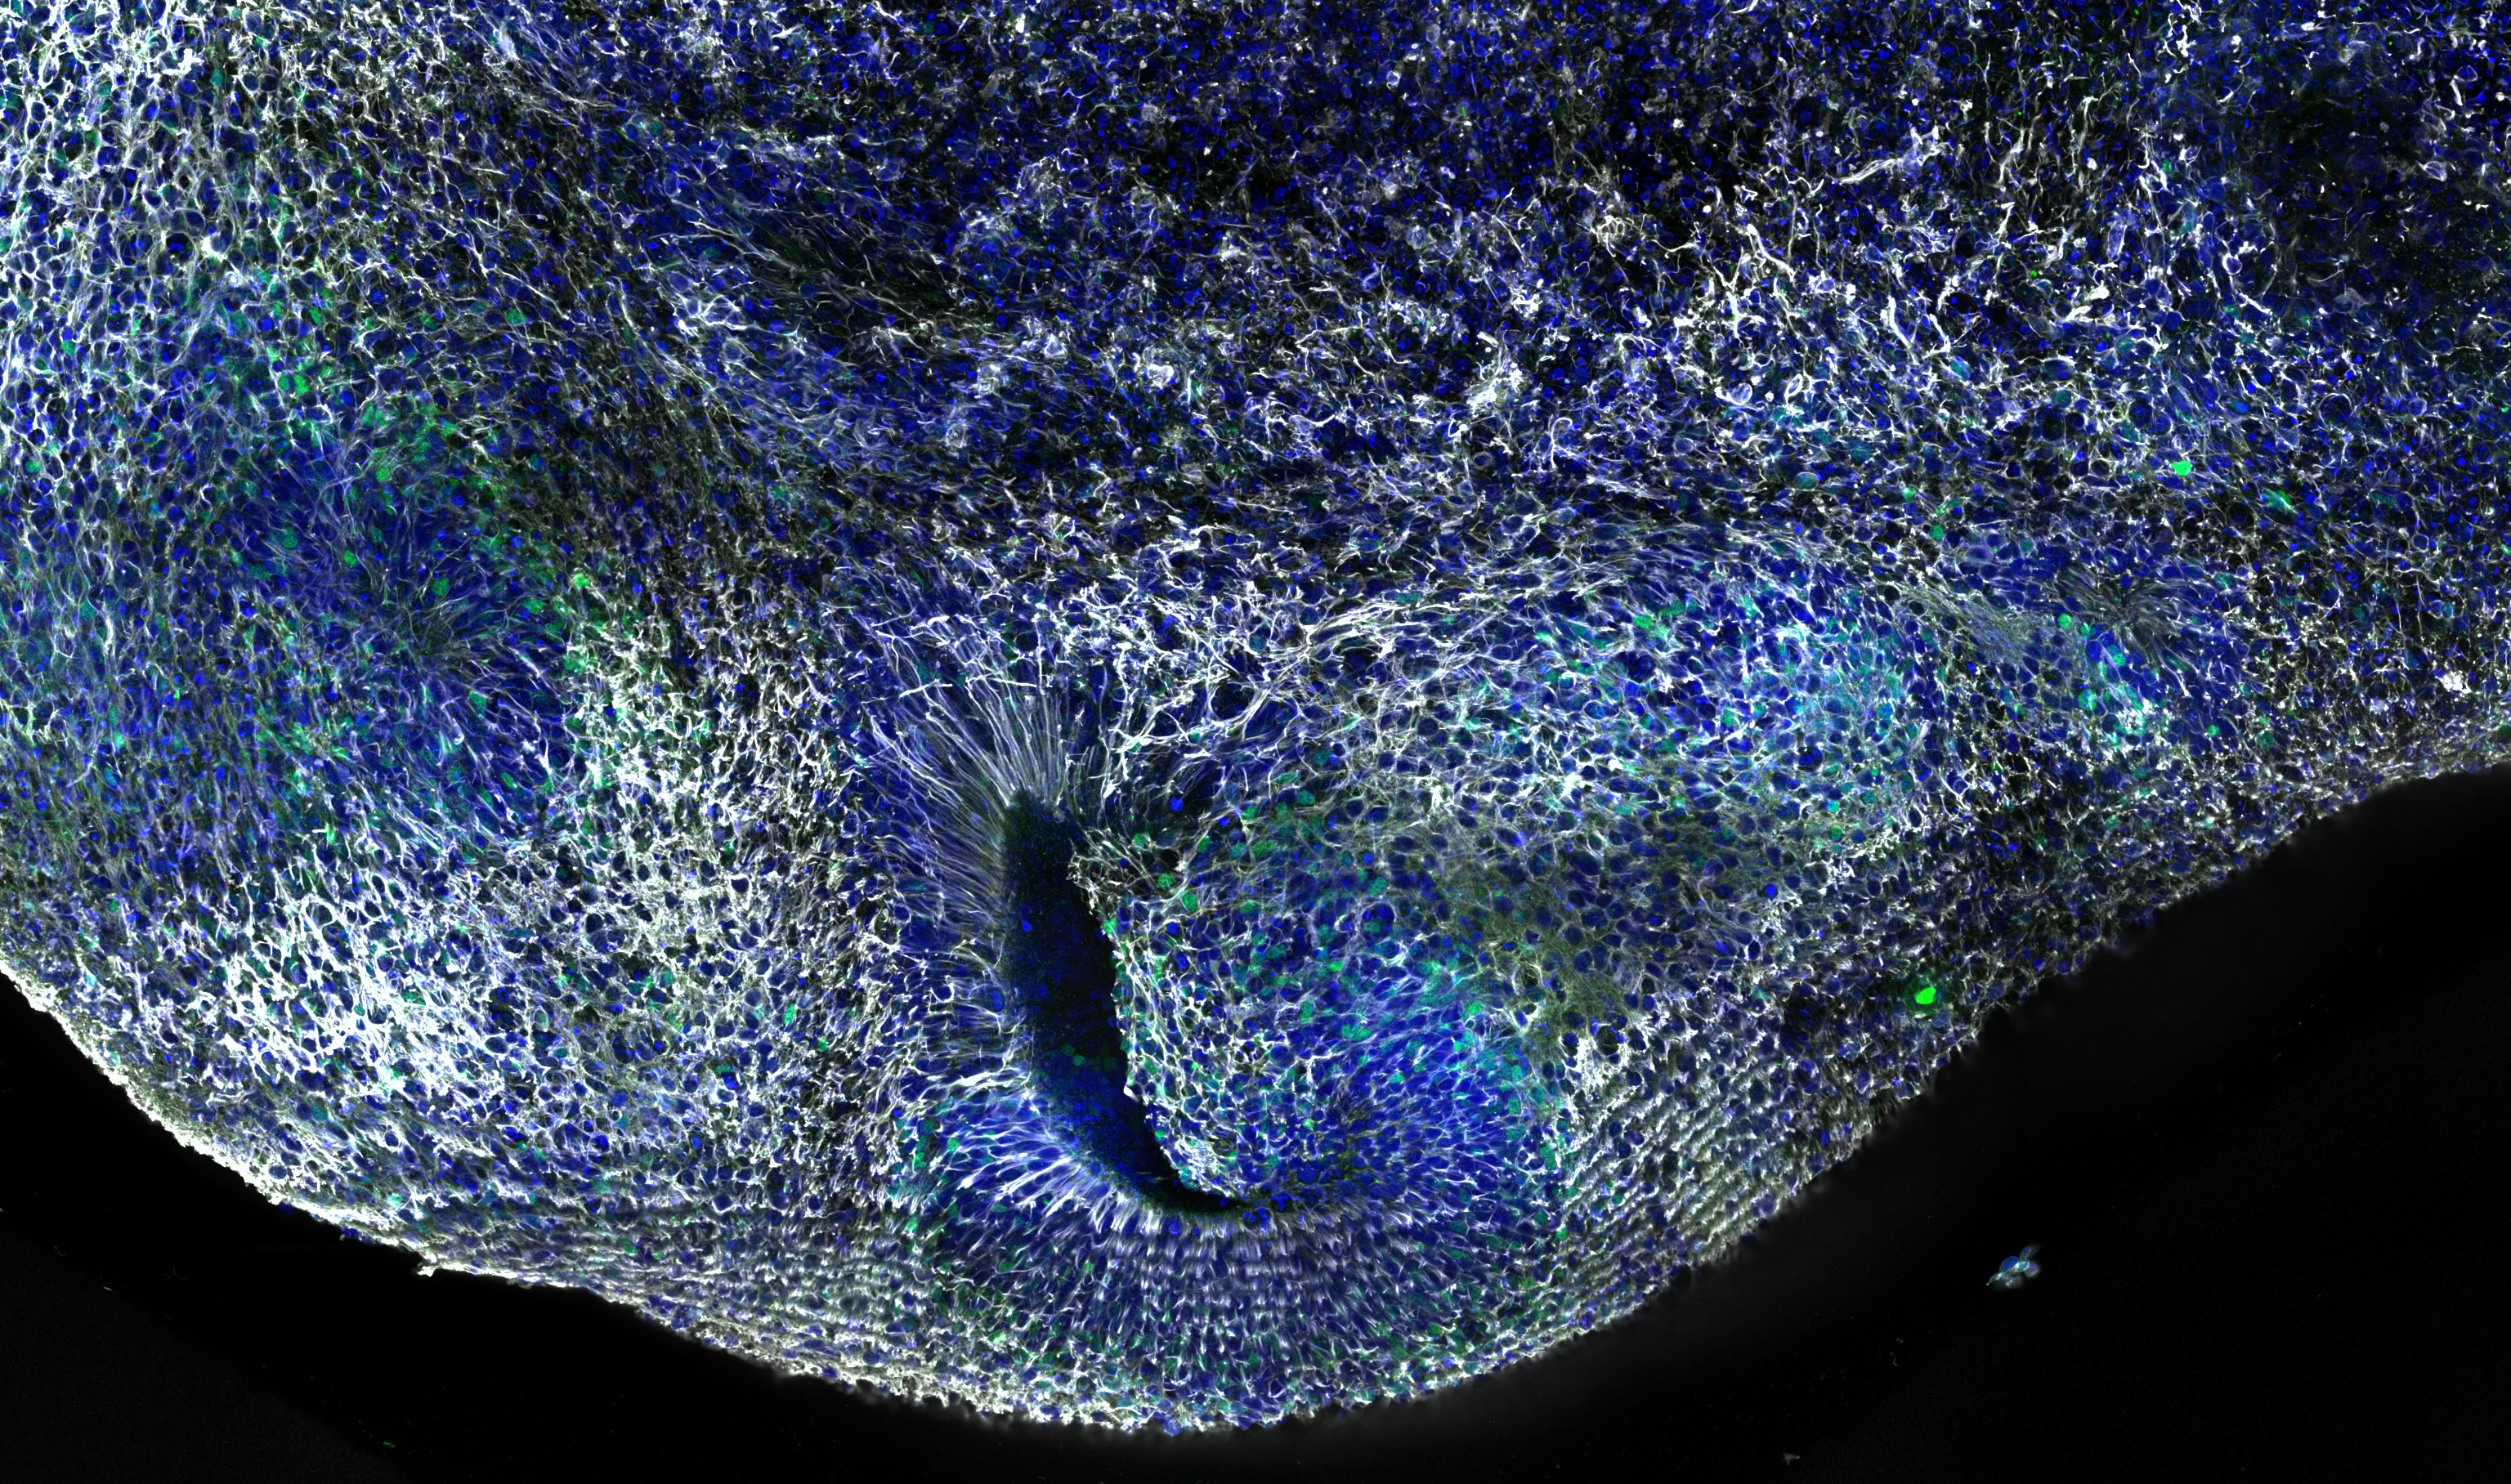

Meet the Expert: Dr. Indra Chandrasekar - Exploring the kidney cellular and organelle architecture using immunofluorescence imaging techniques